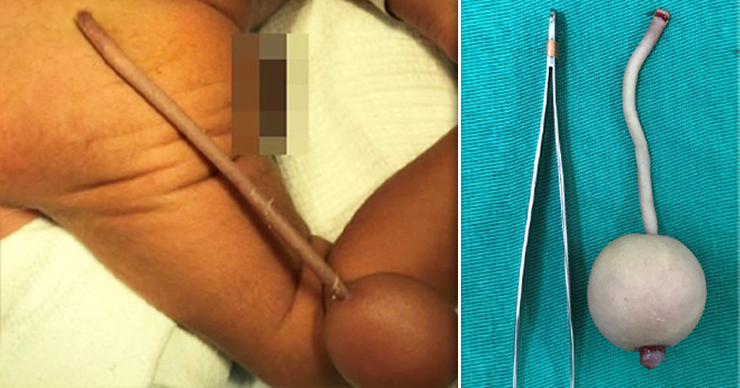

Мальчик родился на 35-й неделе беременности, роды прошли без осложнений, тем не менее у ребенка обнаружили желтуху и хвост длиной около 12 см, при этом на конце хвоста был шарик.

Отметим, что хвост, как правило, появляется у всех людей примерно на четвертой неделе развития, но полностью пропадает к восьмой, превращаясь в копчик. Однако бывали случаи, когда хвосты у людей сохраняются. При этом хвосты бывают как ложными и состоят из жировой или хрящевой ткани, так и истинными – с мышцами, кровеносными сосудами и нервами. В истории медицины известно о 40 случаях истинных хвостов.